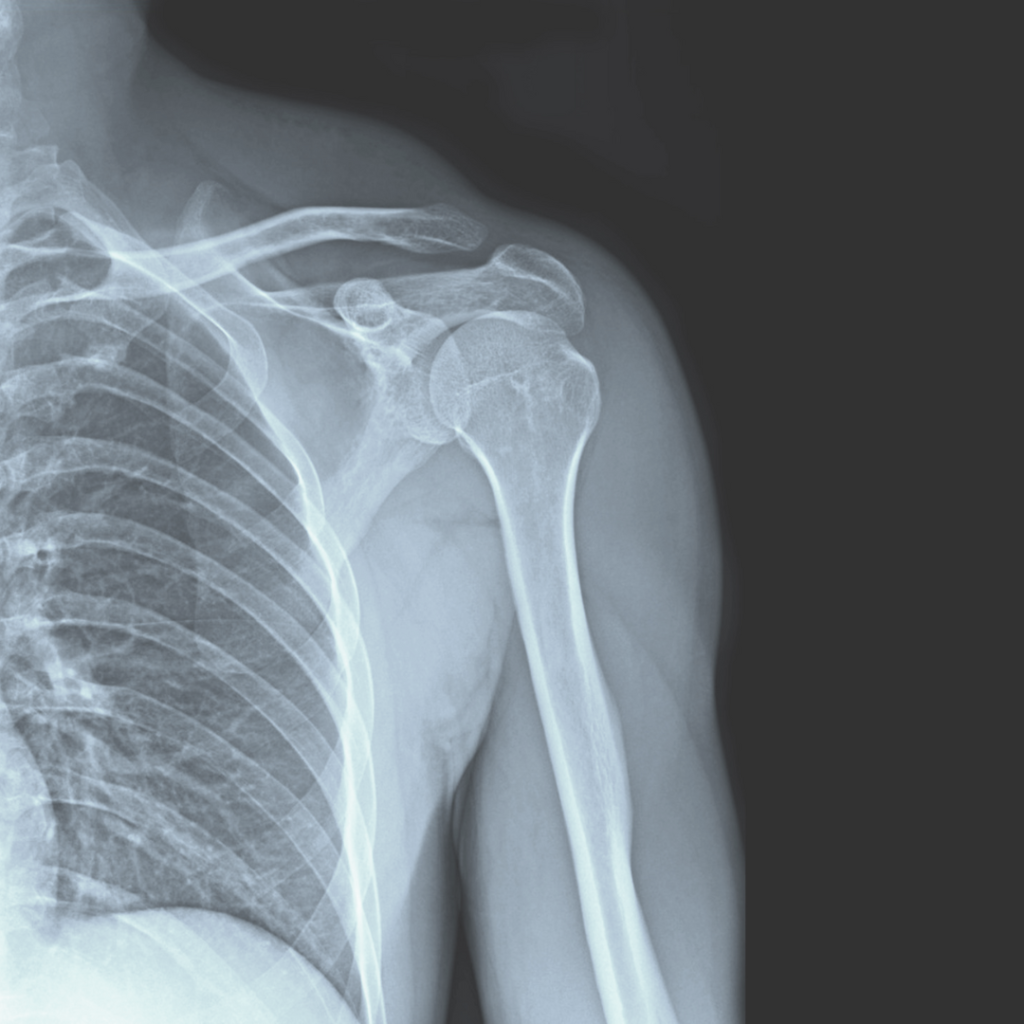

肩関節を構成する骨・軟骨・ 靭帯・腱などが老化して

肩関節周囲の組織に 炎症が起こることが主な原因と考えられています。

「肩の動きが悪くなるような 背中が丸くなる姿勢や動作を 長年続けていくうちに 関節周囲の組織が硬くなり 筋力も低下します。 そして あちこちの骨の動きが 悪くなり 協調性を失います。 そうなると 関節に無理な動きが生じ 組織が擦れたり挟まったりして 炎症を起こす」と。

肩関節の調整だけでなく 肩の動きと関連する 鎖骨・肩甲骨・肋骨・脊椎の動きも確認し それらの調整を行います。